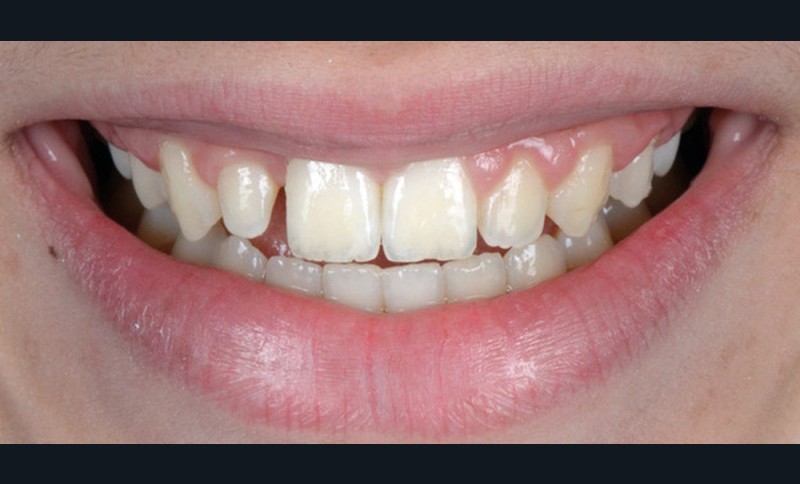

Le Pr Olivier Sorel insistera sur l’importance du respect des formes et des proportions anatomiques, pour éviter de voir apparaître, notamment chez les adultes, de très inesthétiques triangles noirs lors de la phase d’alignement (fig. 6a-b). Il présentera sa démarche diagnostique (évaluation de la forme des dents et de la dysharmonie dento-dentaire, fig. 7a-c) et l’intégration de la réduction amélaire proximale au plan de traitement, afin de s’assurer, en fin de traitement, la présence de papilles gingivales et donc d’un sourire harmonieux (fig. 8a-d).

Les Drs Marie Clément et Clara Marcoux aborderont ensuite les différents apports de la dentisterie esthétique aux traitements orthodontiques. Les problèmes de dyschromies isolées ou généralisées, congénitales ou acquises seront développés ainsi que les anomalies de proportions dentaires (dents riziformes…), le maquillage (transformation d’une canine en incisive latérale…) et le remplacement des dents antérieures. Les auteurs présenteront l’intérêt du Digital Smile Design dans le diagnostic et la communication et l’arsenal thérapeutique à notre disposition pour améliorer la satisfaction de nos patients (éclaircissement, traitement des taches de l’émail, composites stratifiés, fig. 9a-d).